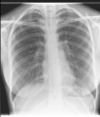

Right lower lobe pneumonia Ccant see right hemi diaphram and heart border with diaphragm Loss of right hemidiaphragm silhouette = right lower lobe involvement Right heart border visible = not primarily right middle lobe More consistent with pneumonia than congestion